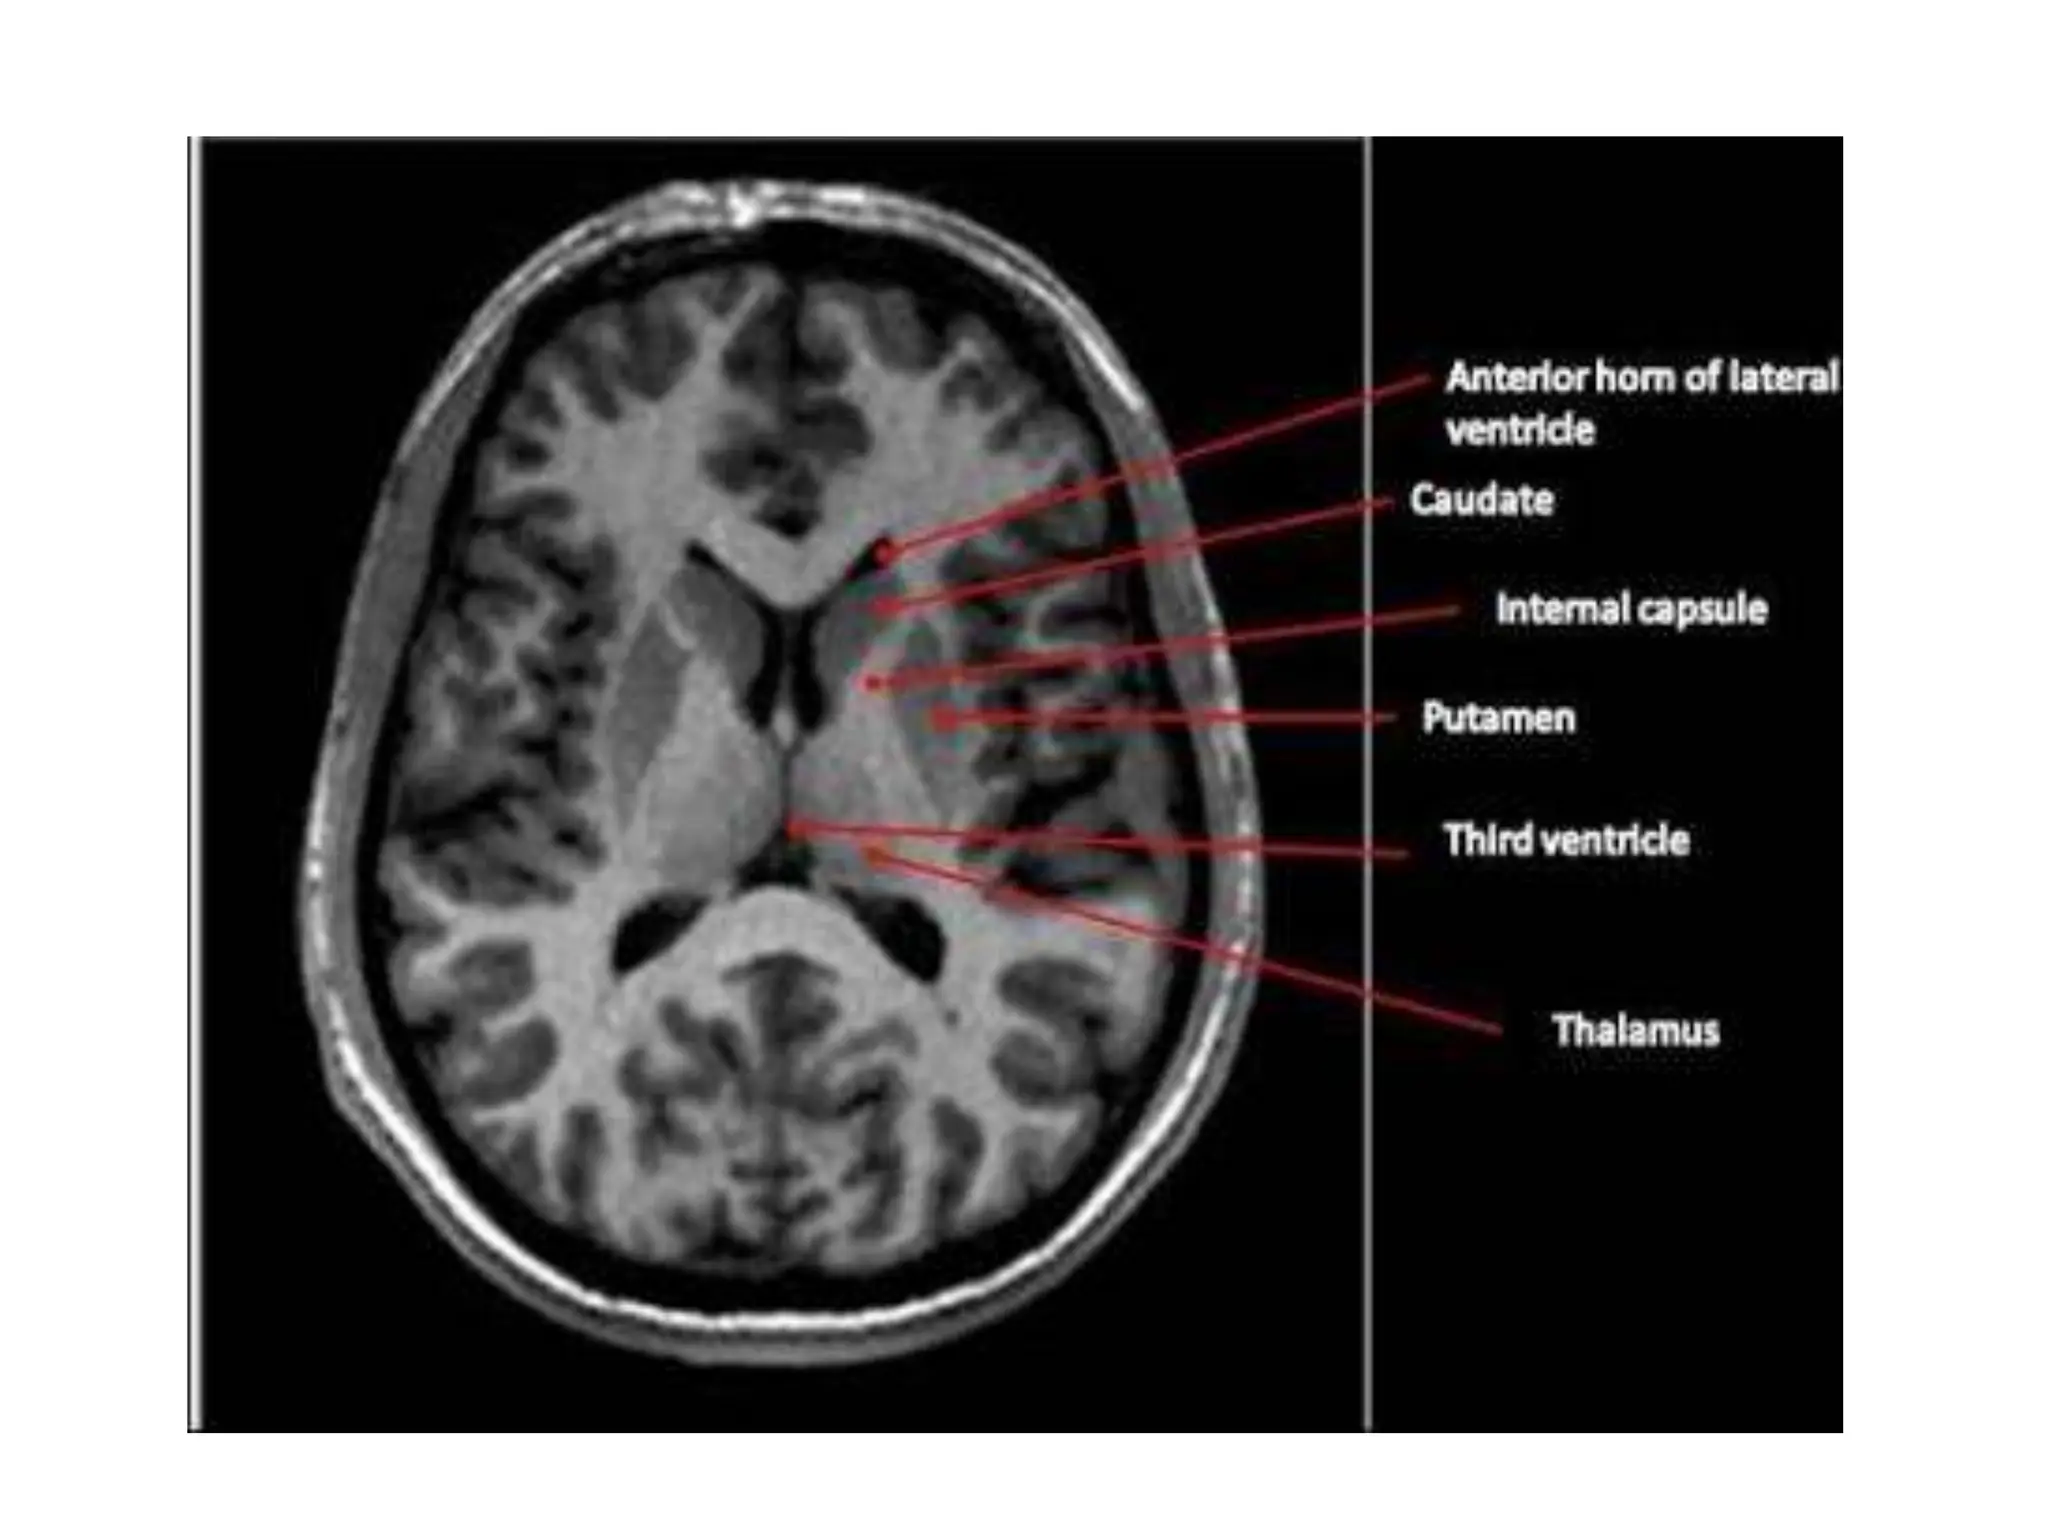

It is intimately related to the lateral

ventricle.

•Head - bulges into anterior horn of

the ventricle and forms its floor. It is

continuous with the putamen.

•The body lies in the floor of the

central part of the ventricle

•Tail in the roof of the inferior horn

of the ventricle.

The body is related

medially to the thalamus

and laterally to the

internal capsule which

seperates it from the

lentiform nucleus.